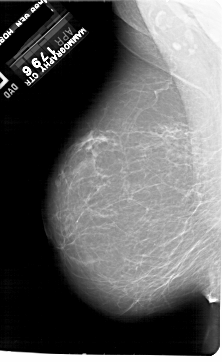

A_1923_1.LEFT_MLO

LEFT_MLO LINES 6871 PIXELS_PER_LINE 4216 BITS_PER_PIXEL 12 RESOLUTION 43.5 NON_OVERLAY